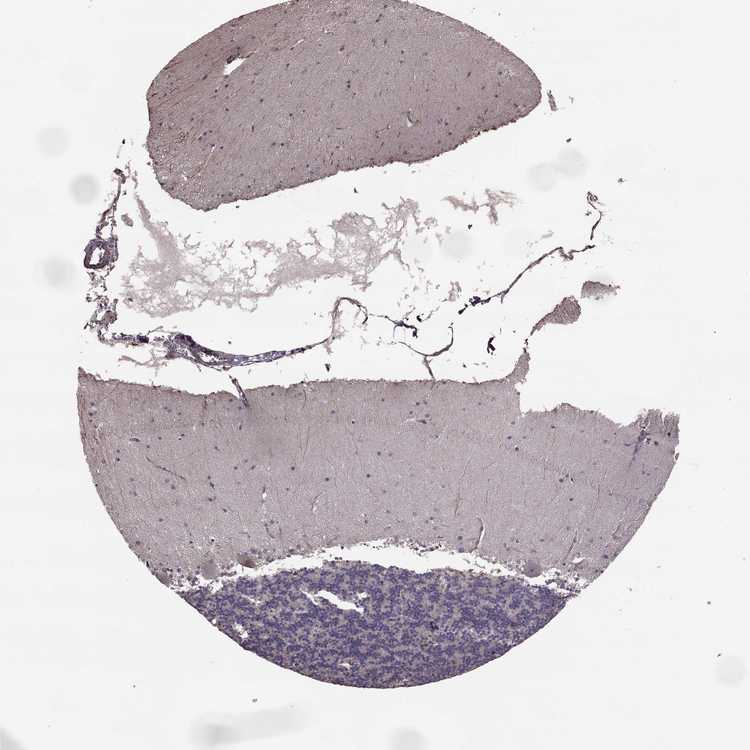

CEREBELLUM - Antibody stainingi

Antibody staining in the annotated cell types in the current human tissue is reported as not detected, low, medium, or high, based on conventional immunohistochemistry profiling in selected tissues. This score is based on the combination of the staining intensity and fraction of stained cells.

Each image is clickable and will lead to virtual microscopy that enables deeper exploration of all samples and also displays staining intensity scores, fraction scores and subcellular localization as well as patient and tissue information for each sample.

Antibody HPA032001

Purkinje cells Not detected

Cells in granular layer Not detected

Cells in molecular layer Not detected